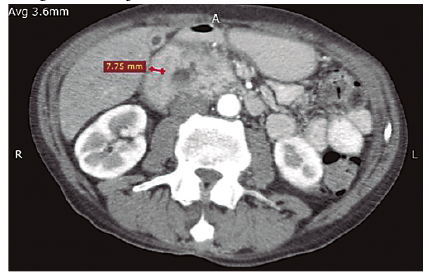

En la TCMD de abdomen con contraste endovenoso se observan imágenes quísticas parietales (Figura 2) y engrosamiento de la pared duodenal con estrechamiento de su luz (Figura 3). Además se logra visualizar a nivel del surco pancreaticoduodenal rarefacción de la grasa y dilatación del colédoco (Figuras 4 y 5).

Afecta predominantemente a varones entre 40 y 50 años con historia de abuso de alcohol, aunque su etiología es incierta.3 El diagnóstico representa un desafío para el médico radiólogo, que frente a una masa de morfología laminar entre la cabeza pancreática y la segunda porción duodenal, que se presenta en la TCMD como una formación hipodensa (Figura 4) acompañada de engrosamiento concéntrico de la pared duodenal con estenosis de su luz,4 y presencia de formaciones quísticas en la pared del mismo.5 (Figuras 2 y 3), debe reconocer los múltiples diagnósticos diferenciales, como el carcinoma ductal pancreático y el carcinoma duodenal.